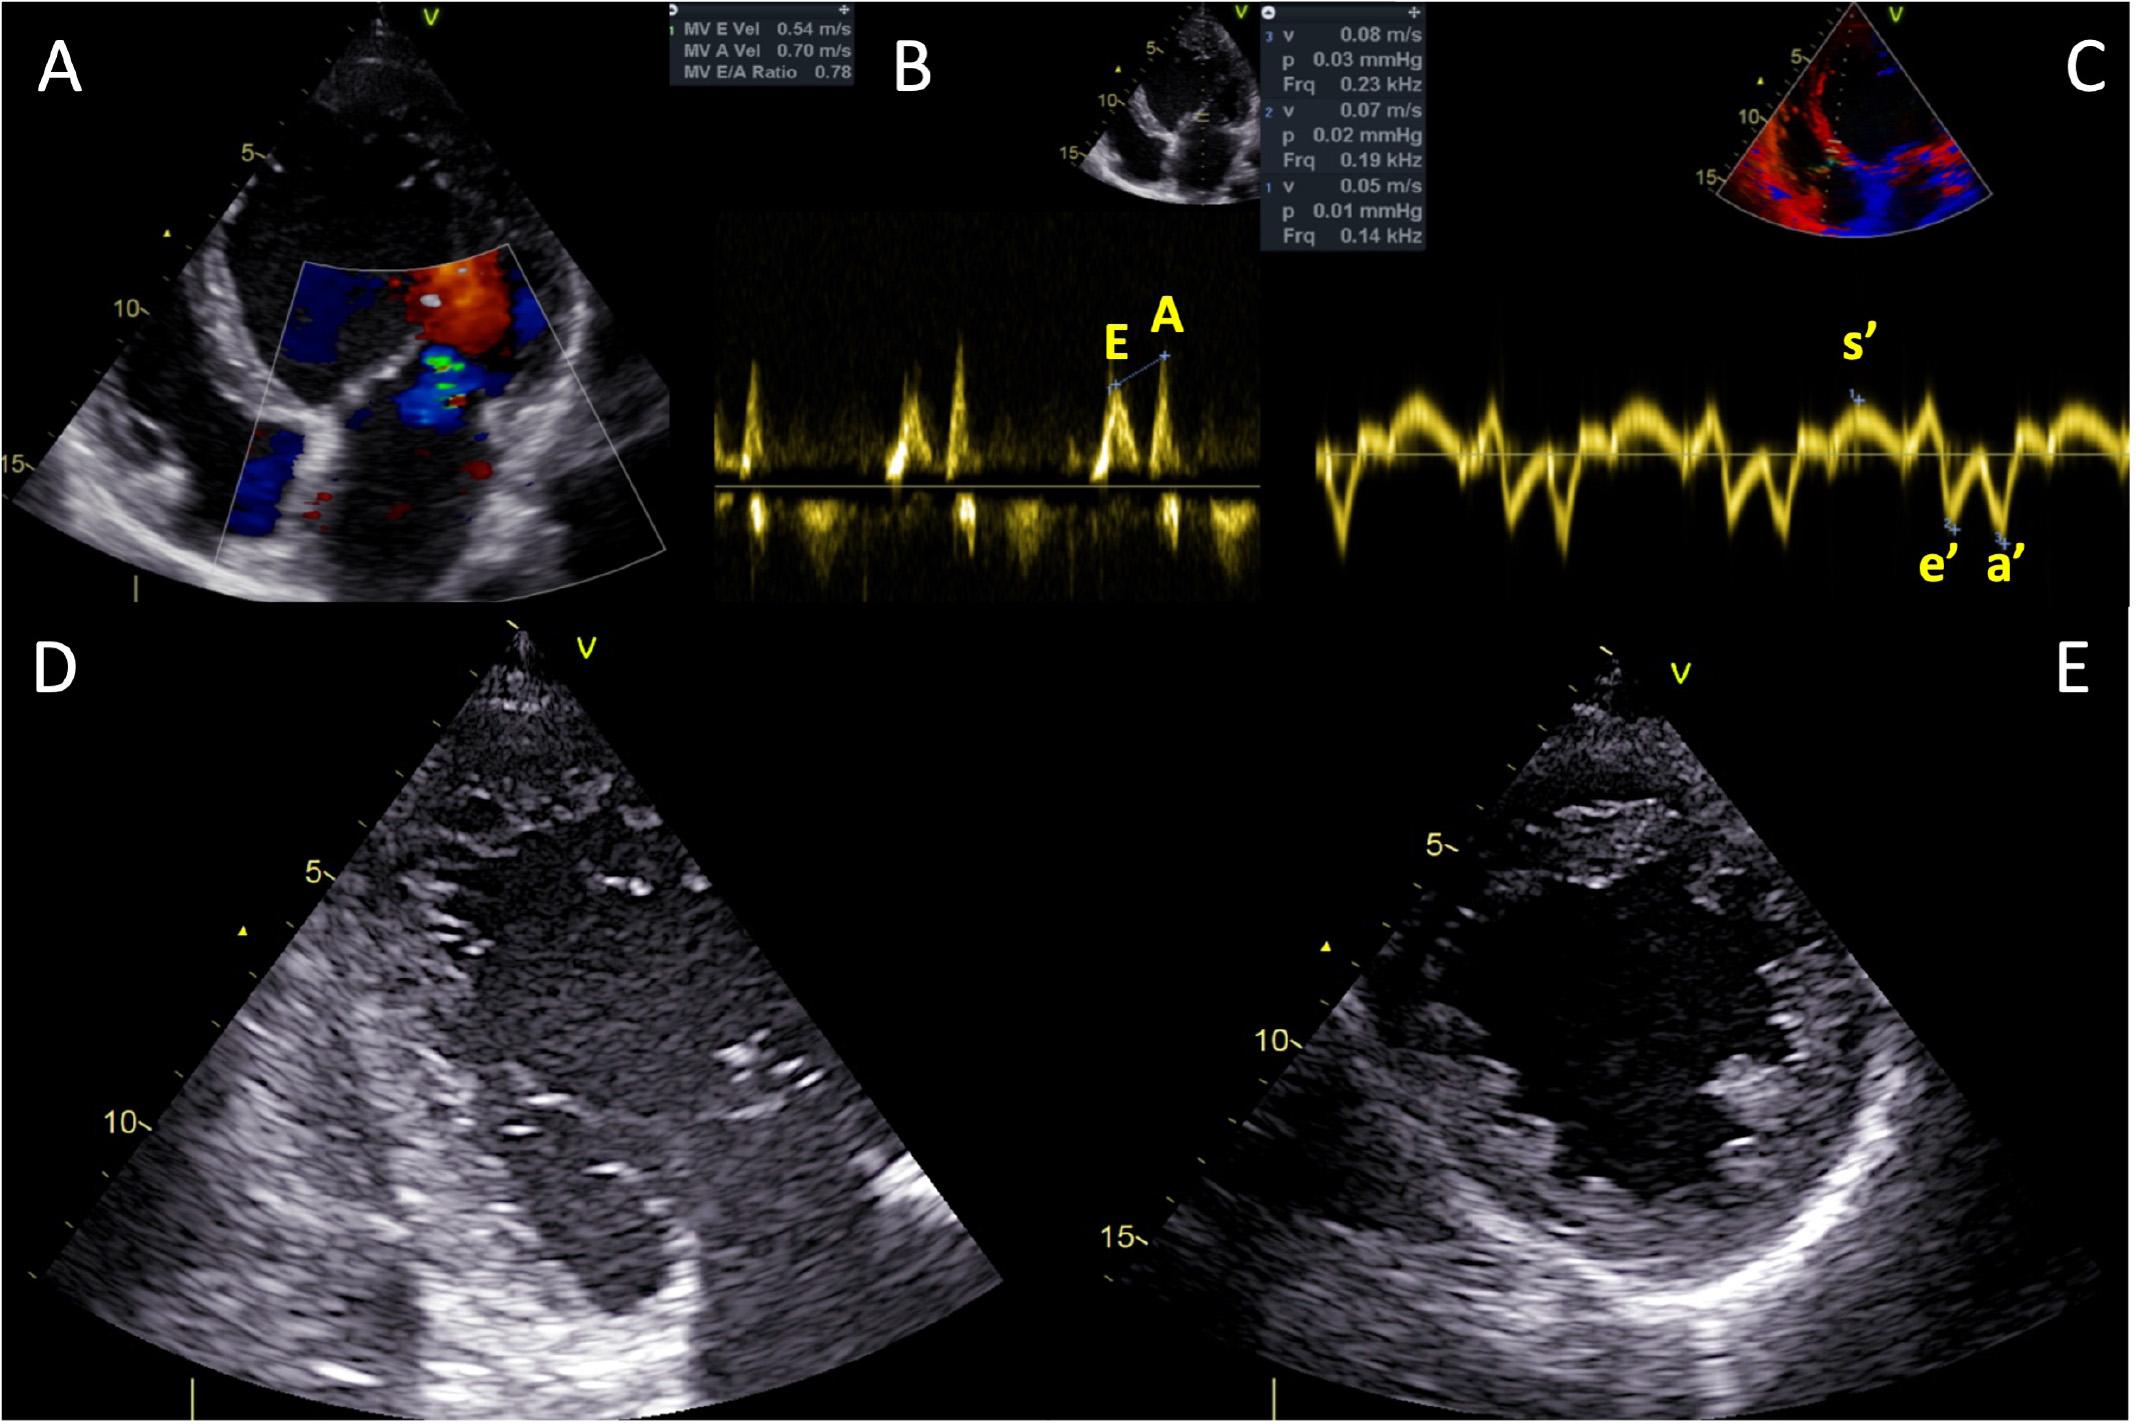

Figure 4